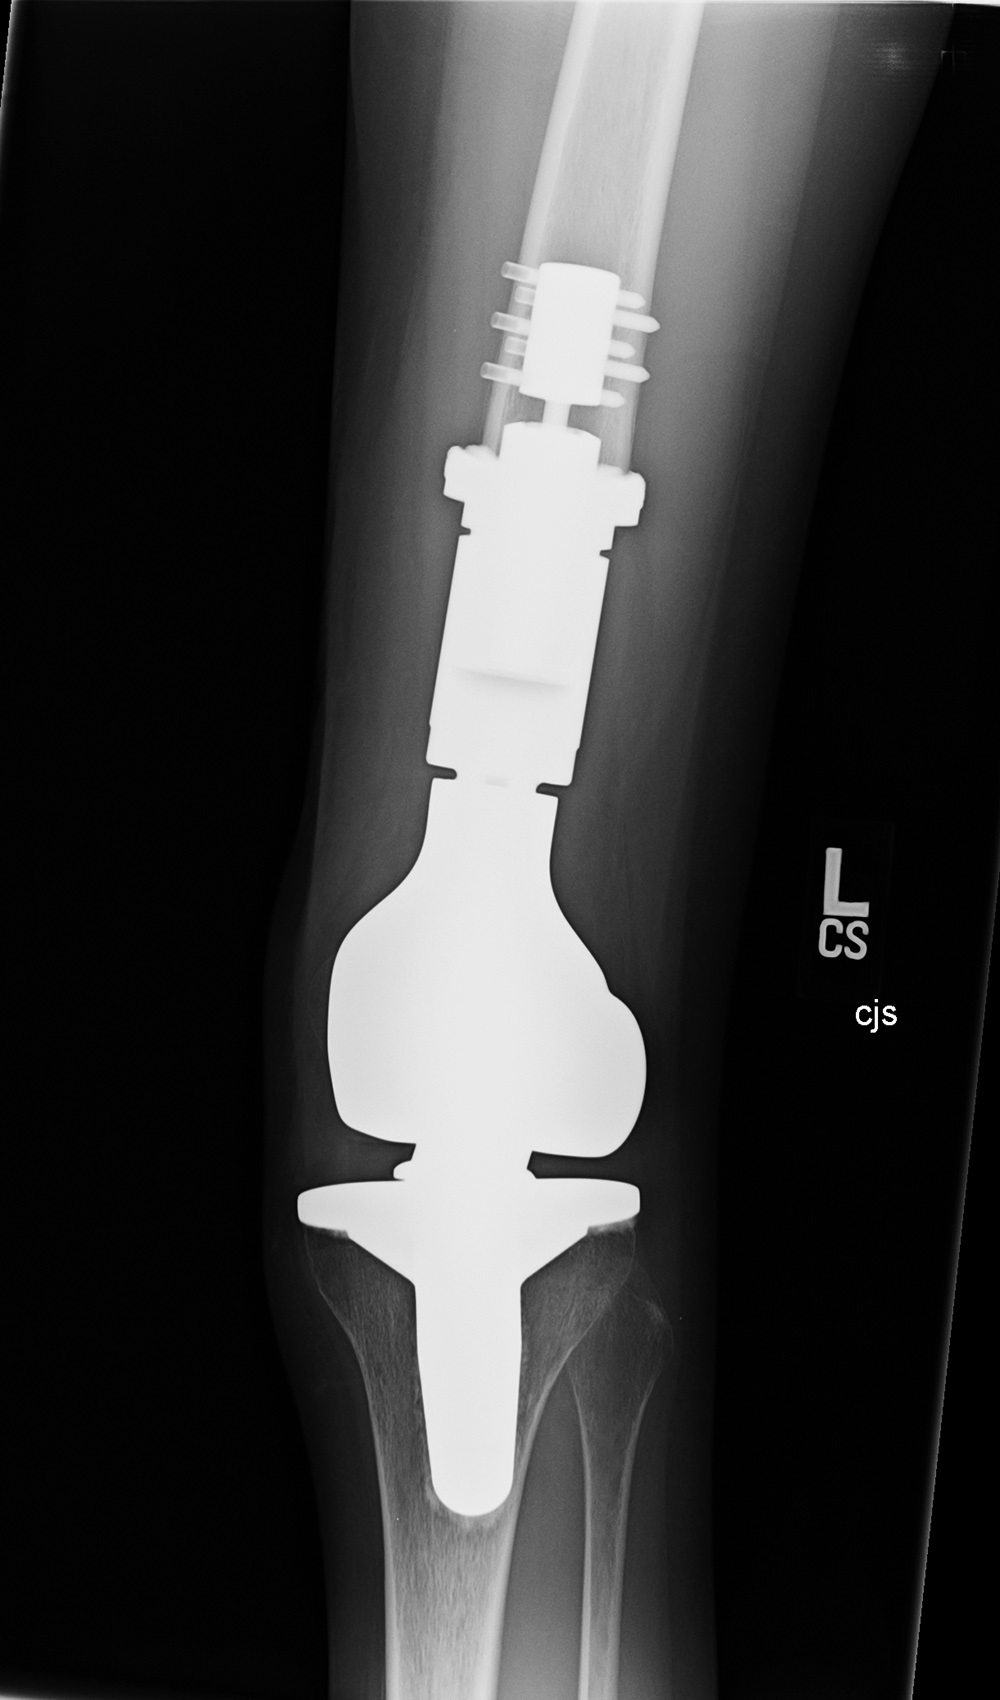

Limb sparing (salvage) prosthesis Varus-valgus lower limb salvage prosthesis (limb-salvage total knee arthroplasty)

Limb sparing prosthesis Limb sparing prosthesis lateral view Lower limb salvage prosthesis Lower limb salvage prosthesis

17 year-old woman with Ewing sarcoma treated with limb sparing prosthesis This is a custom made prosthesis for a patient who was treated for a Ewing sarcoma. From Taljanovic, 2005